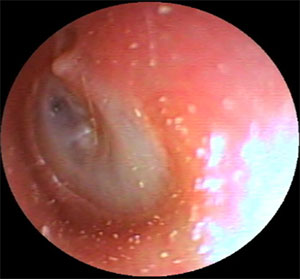

| 左外耳道炎 | ||

| 治療前 | 治療後 | |